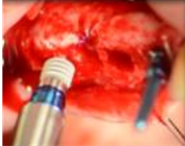

Técnica por abordaje crestal: Técnica de Summers. Consiste en realizar la osteotomía para el implante hasta 1mm subantral e impactar el suelo sinusal con osteótomos, permitiendo obtener incrementos de altura de 2 a 5 mm. Esta técnica también muestra alto índice de sobrevida, similar a la técnica tradicional11. Se recomienda para una altura mínima de 5mm de hueso residual9. Un problema de esta técnica es que la perforación de la membrana puede pasar inadvertida, por lo que no se recomienda colocar substitutos óseos11.